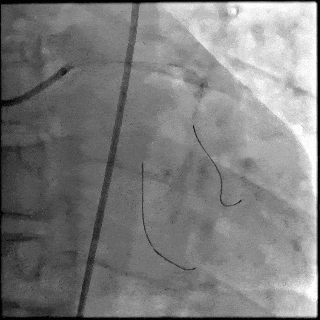

5月28日8:00,葛均波院士团队在中山医院16号楼16楼中伟厅成功连线喀什二院导管室,沪喀远程手术正式开始。8:35,新疆喀什二院导管室内股动脉入路通路建立后,行左右冠脉造影示左前降支中段存在85%的严重狭窄,狭窄位于血管分叉路口且紧邻心肌桥;且左回旋支中段近乎闭塞,血管细窄且迂曲,病变弥漫。8:59,葛院士于上海操控血管介入机器人主端,将指引导管送至左冠脉开口,并操控主支导丝和分支血管保护导丝通过狭窄病变,后送至前降支和对角支血管远端以建立轨道,同时利用介入机器人的微速调整功能避开心肌桥,以亚毫米级精准定位释放1枚支架。在成功处理患者左前降支病变后,葛院士通过搓捻机械操纵杆,远程精细调整导丝“进攻”方向,顺利通过左回旋支次全闭塞病变。因血管相对细小且病变弥漫,葛院士决定采用单纯球囊扩张术处理,即刻造影提示几乎无残余狭窄,避免了额外的支架植入。10:10,撤出所有导丝及导管,手术顺利结束。

【DSA图1.左冠治疗前造影】